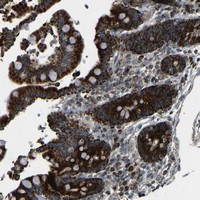

Supportive validation

- Submitted by

- Abnova Corporation (provider)

- Main image

- Experimental details

- Immunohistochemical staining of human colon with C12orf39 polyclonal antibody (Cat # PAB20633) shows strong cytoplasmic positivity, with a granular pattern, in glandular cells at 1:50-1:200 dilution.

- Validation comment

- Immunohistochemistry (Formalin/PFA-fixed paraffin-embedded sections)